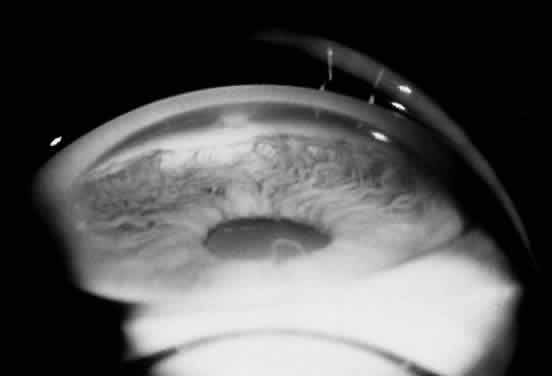

Ocular manifestations of the Axenfeld-Rieger syndrome include the presence of posterior embryotoxon and iris strands that attach to Schwalbe's line (Fig. 11). If the iris is normal, the condition is termed Axenfeld's anomaly. If iris defects are present, then it is classified as Rieger's anomaly. Iris findings in Rieger's anomaly may range from mild hypoplasia to full-thickness hole formation (Fig. 12). Glaucoma develops in approximately 50% to 60% of patients with Axenfeld-Rieger syndrome. When Rieger's anomaly is associated with systemic anomalies, it is known as Rieger's syndrome. Developmental abnormalities seen in Rieger's syndrome commonly affect the teeth and facial bones. These defects may include microdontia, hypodontia, and maxillary hypoplasia. Originally described as separate clinical entities, Axenfeld's and Rieger's anomaly are now considered to be variations in the spectrum of the same developmental disorder.

Fig. 11. Gonioscopic view of the iris processes in Axenfeld-Rieger syndrome. (Courtesy of James J. Reidy, MD)

A late arrest in the development of anterior chamber structures derived from neural crest cells is responsible for the ocular defects seen in Axenfeld-Rieger syndrome. Contracture of an abnormally retained primitive endothelial layer on the surface of the iris and anterior chamber angle, deposition of basement membrane by these endothelial cells, and incomplete development of the trabecular meshwork and Schlemm's canal are thought to be responsible for the iris changes, prominent Schwalbe's line, and glaucoma that are seen in this disorder. The systemic malformations seen in Rieger's syndrome are also secondary to a defect in neural crest cell development.